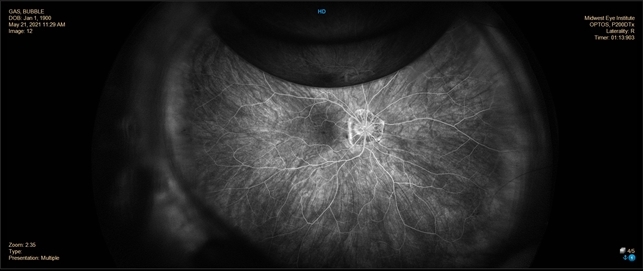

What Happens To The Gas Bubble In Retina Surgery

What Happens To The Gas Bubble In Retina Surgery

Intravitreous Gas Bubbles Retina Image Bank